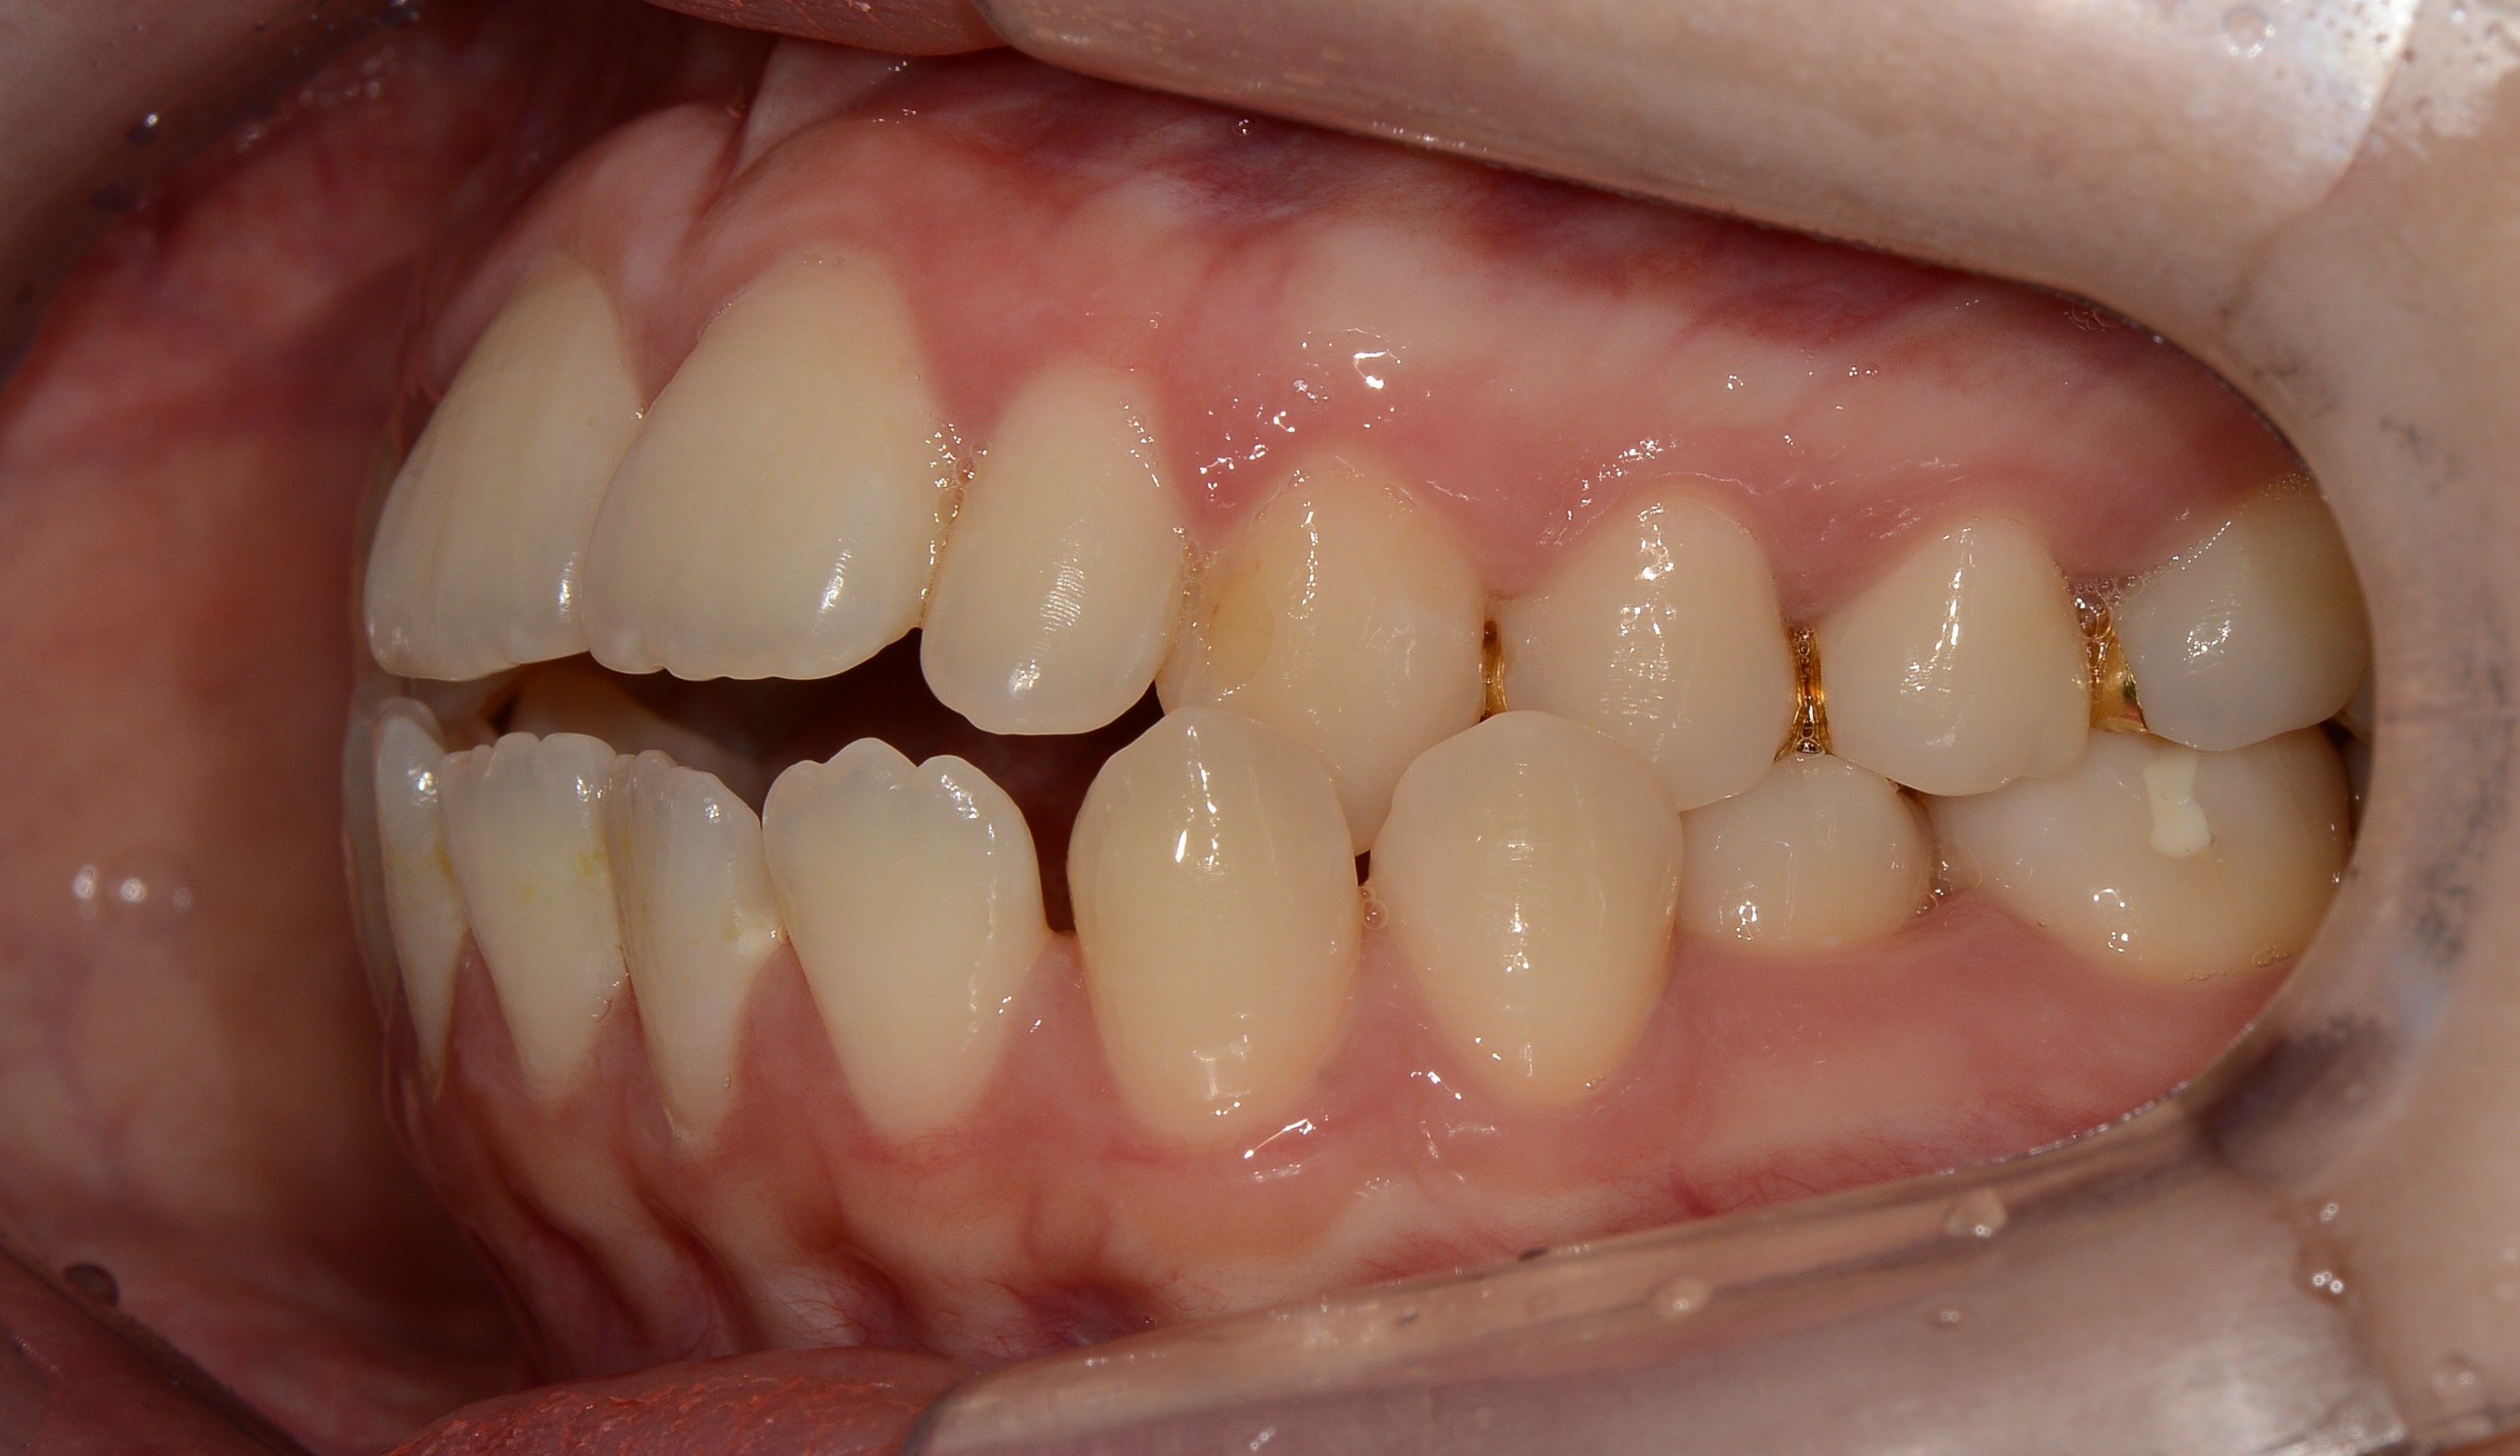

치료 후 사진입니다.